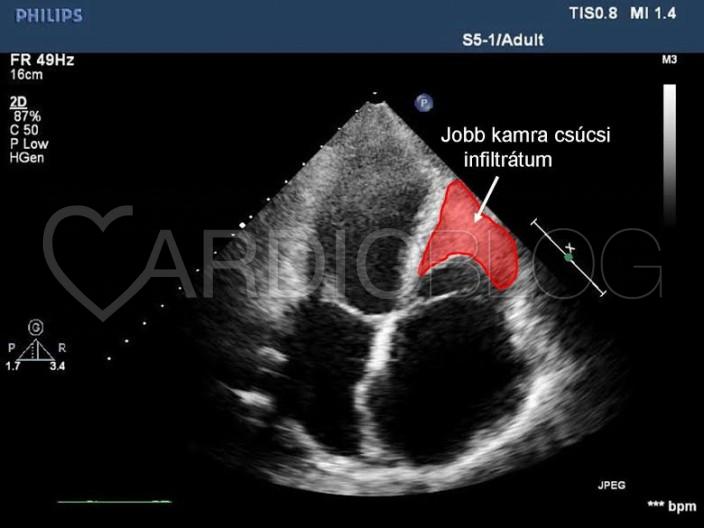

A normál tágasságú jobb kamra csúcsában endocardium megvastagodást és infiltrátumot láttunk (2. ábra, 1. videó), mely restriktív funkciózavart okoz, diasztolés D-jellel (2. videó), közepes fokú tricuspidális regurgitációval.

Az elvégzett MRI vizsgálat normális bal és jobb kamrai volumeneket és ejekciós frakciókat írt le, jobb kamra csúcsi és bal kamra subvalvuláris endocardium megvastagodással, mely Löffler kórnak megfelel. A beteg panaszai és a látott kép alapján felmerült a sebészi endocardiectomia lehetősége (a megvastagodott, fibrotikus endocardium „lehámozása”), további kivizsgálásig a beteget hazaengedtük.

A Löffler kór a hypereosinophil szindróma kardiális manifesztációja, ami endomyocardiális fibrosis révén restriktív cardiomyopathiát okoz. Főként a kamrák csúcsi része, és a subvalvularis régió érintett. Ha a kamracsúcs érintett, gyakran látható benne thrombus. Tünetei lehet a jobb, illetve balszívfél elégtelenség, mitrális regurgitáció, szisztémás

embolizáció. Echocardiográfiával látható a megvastagodott endocardium, a csúcsi thrombus, restriktív diasztolés diszfunkció, mitrális, vagy tricuspidális regurgitáció. Gyógyszeres kezelésében corticosteroid, hidroxyurea és infterferon terápia jön szóba, thrombus esetén anticoagulálás szükséges. Gyógyszeres kezelés hatástalansága és progrediáló szívelégtelenség esetén sebészi endocardiectomia jön szóba.